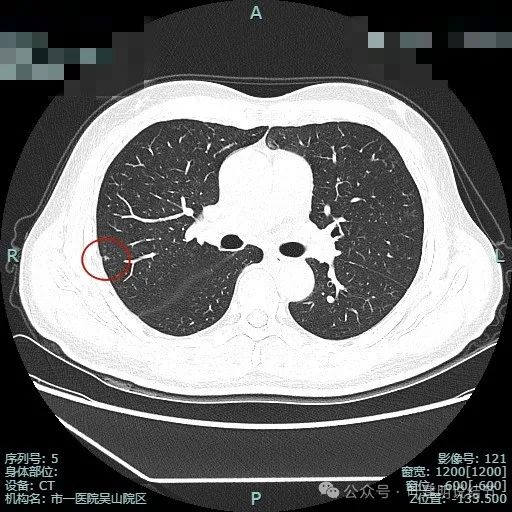

先来看两肺多发结节的总体情况:

病灶1:左上叶肺尖淡磨玻璃影,轮廓稍显模糊,少许慢性炎或肺泡间隔增宽可能性大。

病灶2:右上肺胸膜下微小磨玻璃结节,表面欠光滑,倾向肺泡上皮增生之类的病变,目前不十分确切,但风险总是低的。